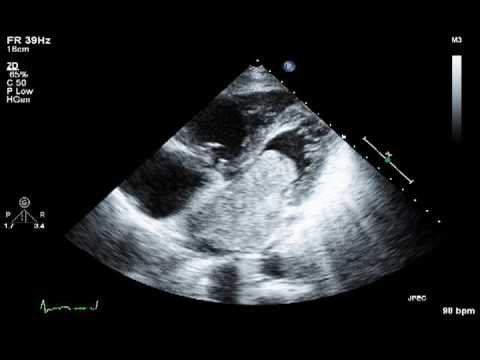

Bác sĩ có thể chỉ định các Xét nghiệm như điện tim, siêu âm tim, Chụp CT tim hoặc MRI tim để chẩn đoán.